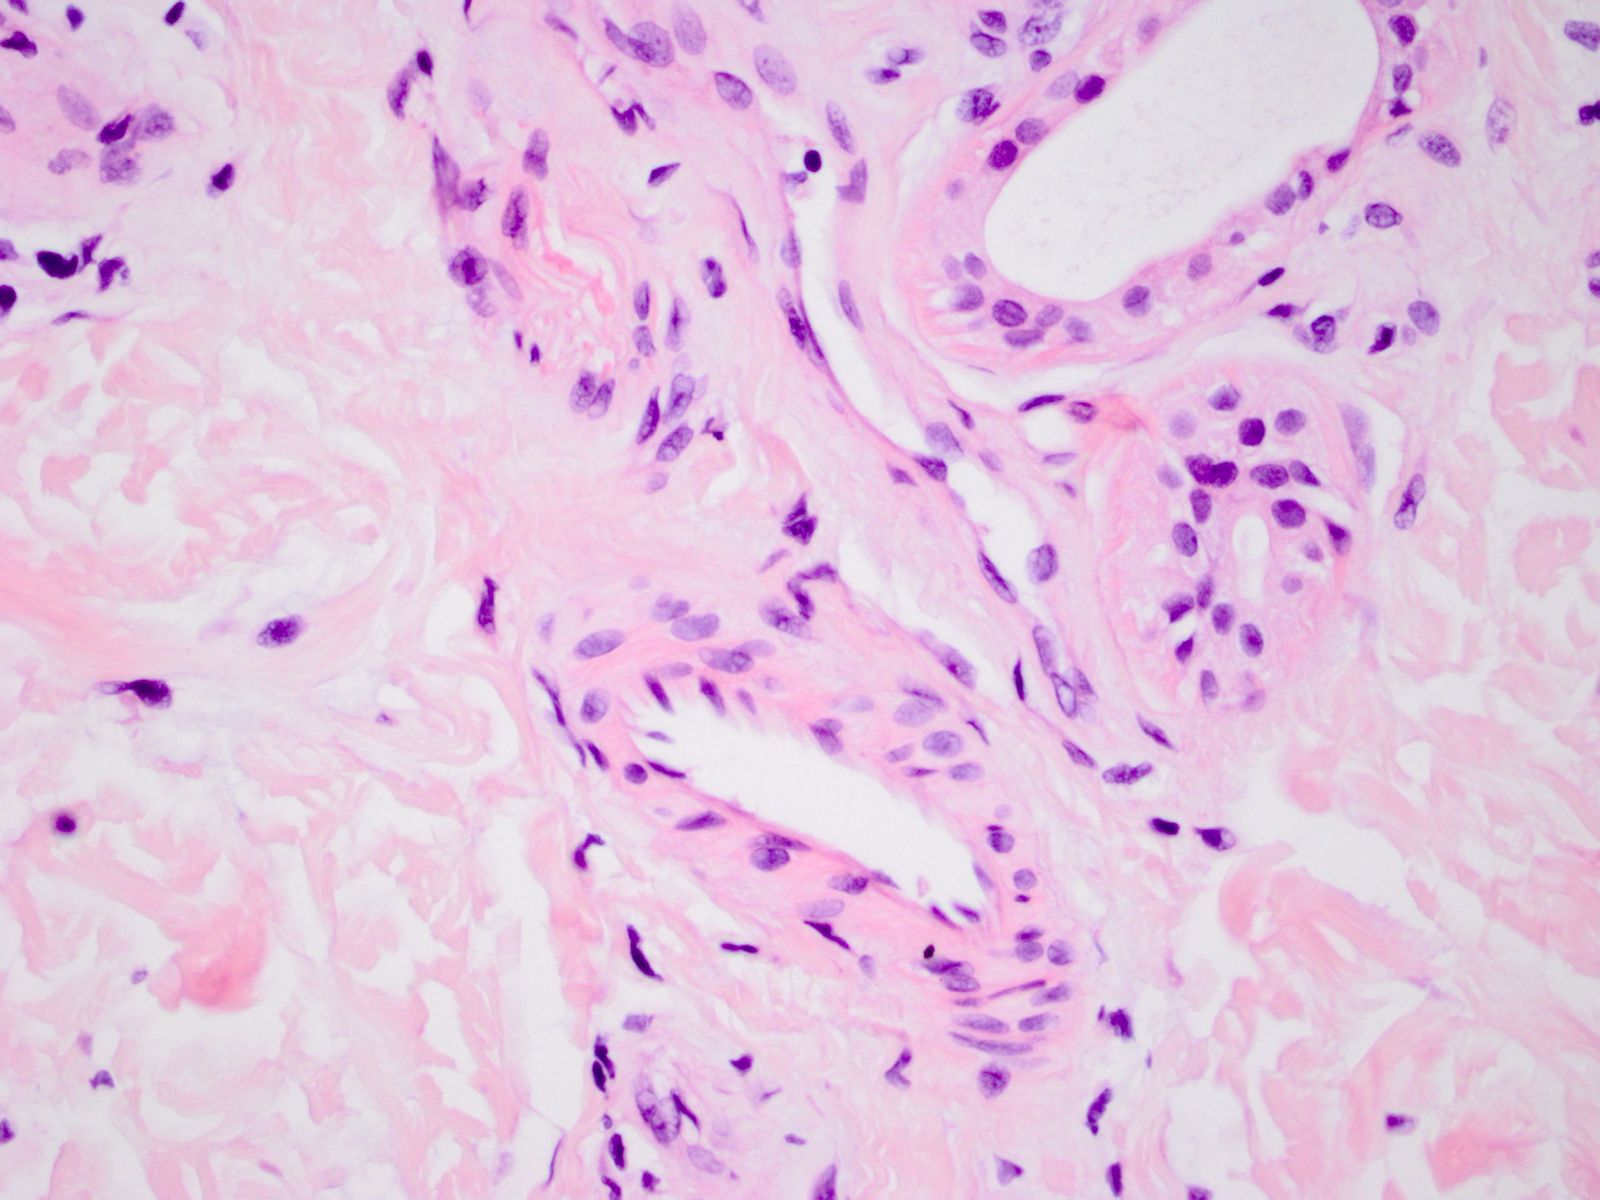

![Talgklieren (click on photo to enlarge) [source: www.huidziekten.nl] Talgklieren](../../../images/talgklieren-1z.jpg) |

![Talgklieren (click on photo to enlarge) [source: www.huidziekten.nl] Talgklieren](../../../images/talgklieren-2z.jpg) |

| talgklieren |

talgklieren |